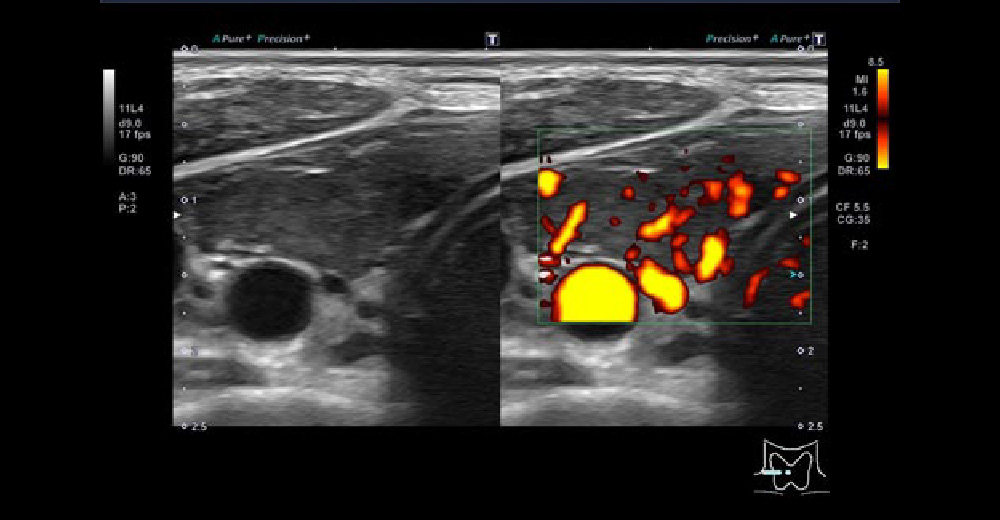

ドップラーエコーにて甲状腺内部血流がびまん性に異常豊富となり、上甲状腺動脈の流速が60m/s程度となっている症例です。

バセドウ病 バセドウ病